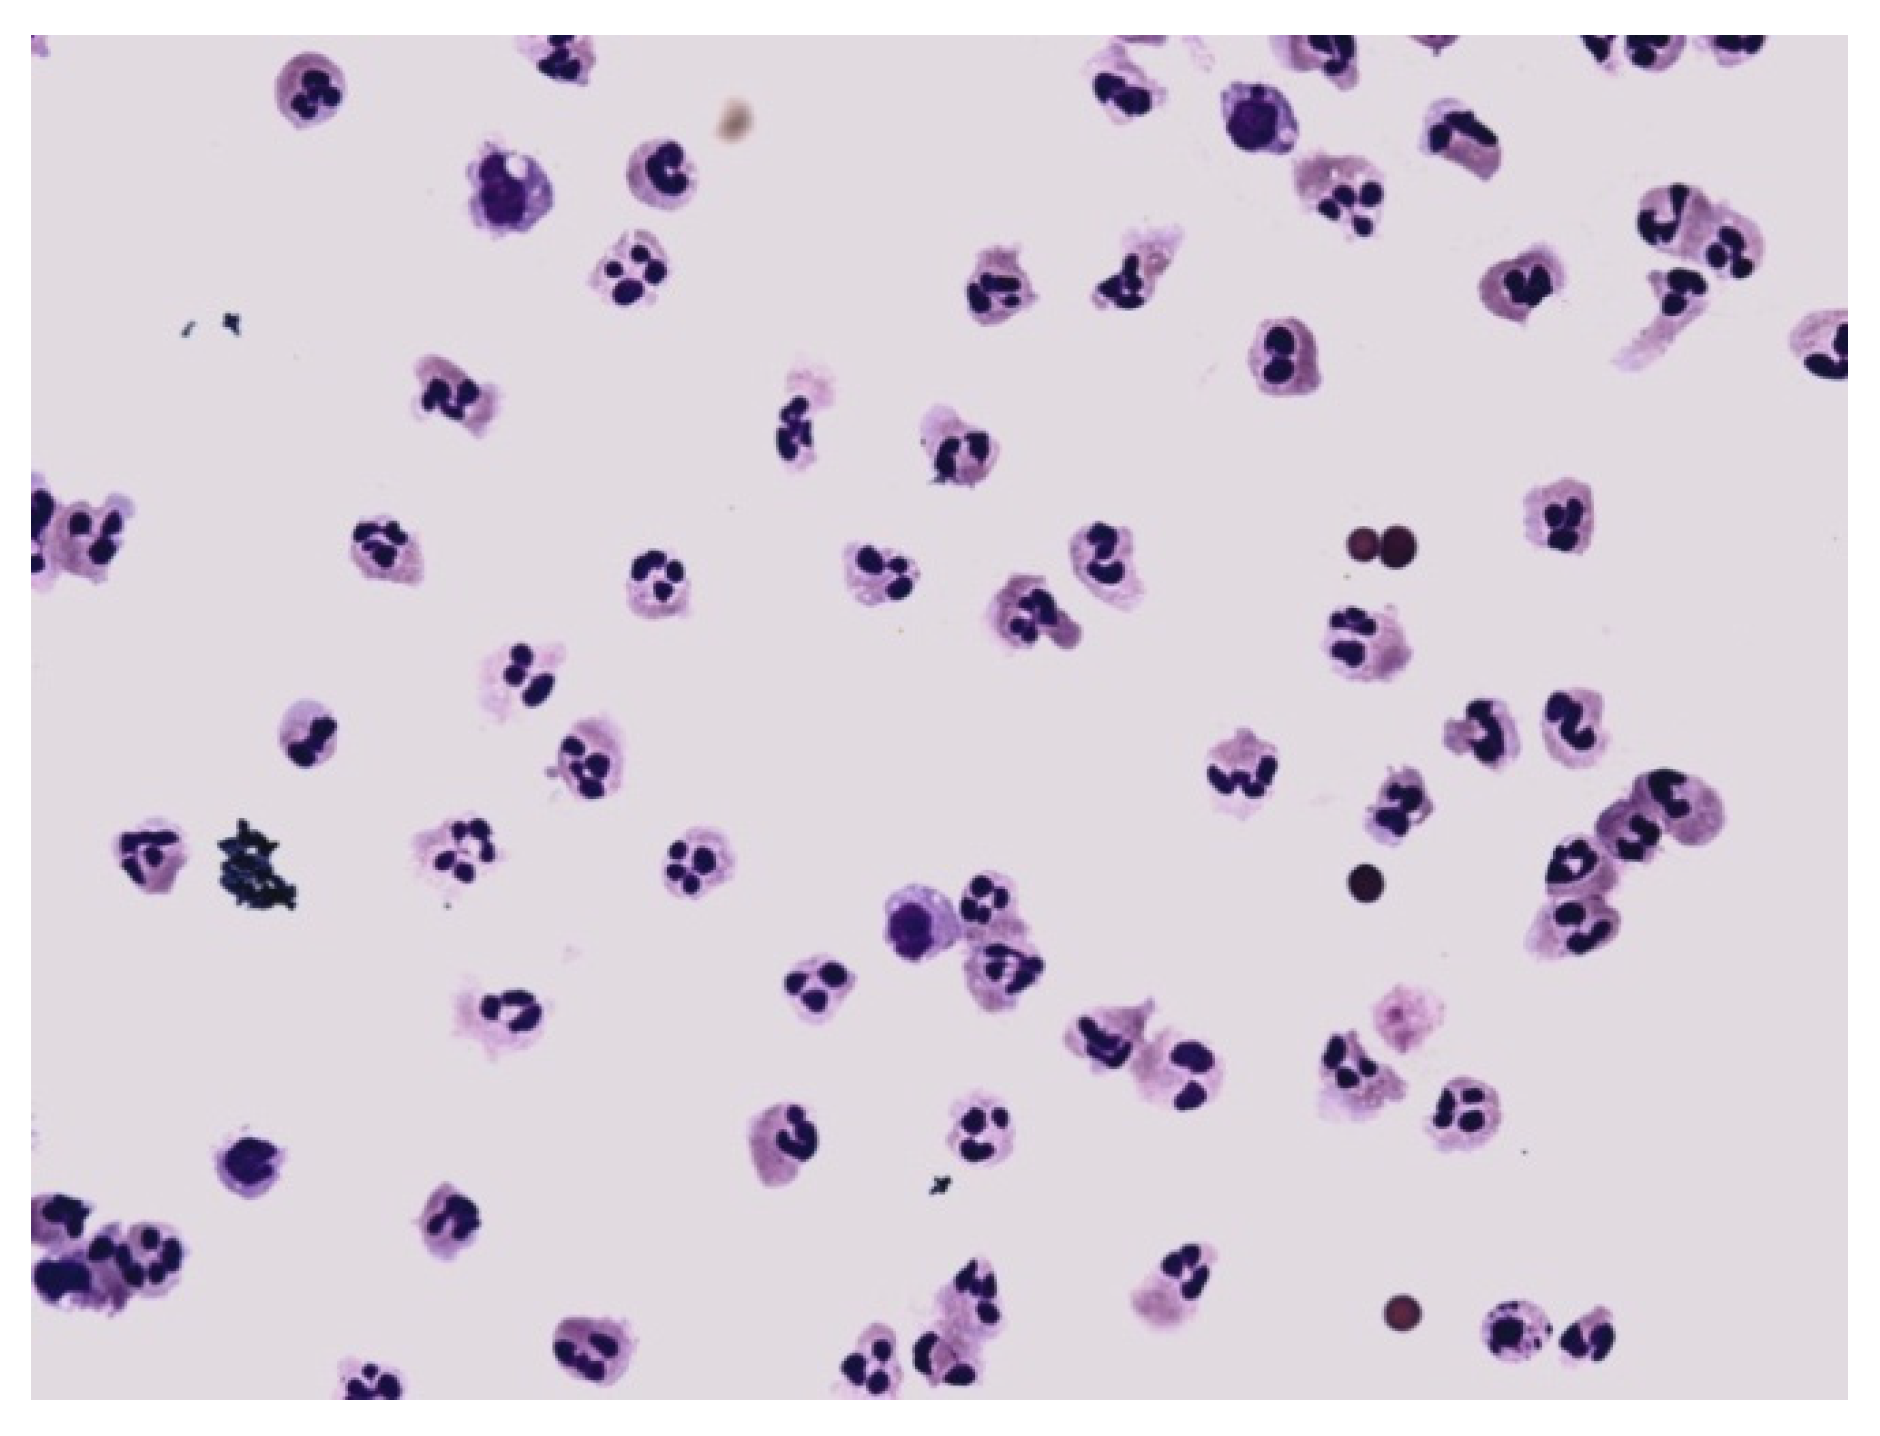

Figure 12.

Predominance of neutrophils in synovial fluid; KEB = 32.7; non-purulent response in the knee joint after traumatic distortion.